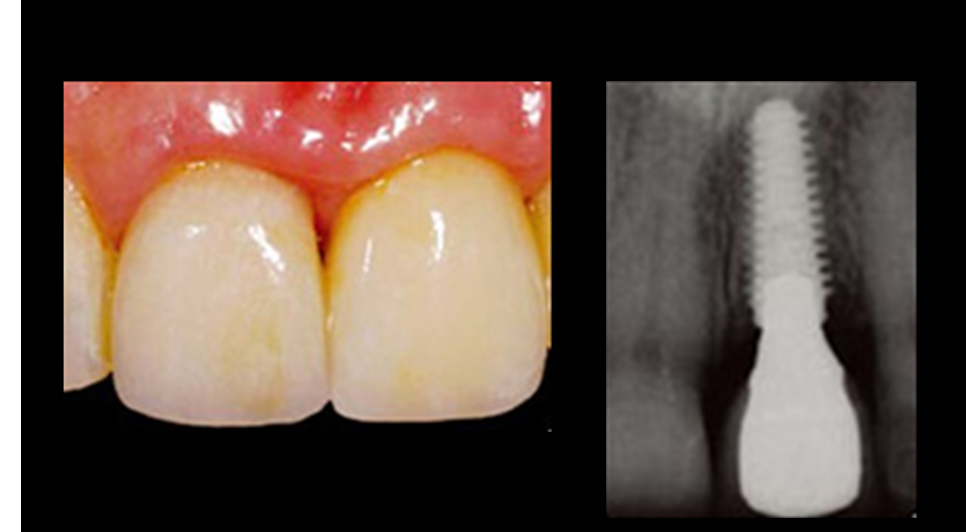

“Immediate loading of single AnyRidge implants

is a highly successful treatment modality. ”

Clinical case: Immediate post-extraction insertion of implant & immediate loading

- Courtesy of Prof. Giuseppe Luongo, Italy -

AnyRidge, immediate loading, single implant, multicenter study, maxillary anterior, Prof. Giuseppe Luongo, single replacement

AnyRidge implant system

Reference

Immediate functional loading of single implants: a multicenter study with 4 years of follow-up

/J Dent Res Dent Clin Dent Prospect 2018; 12(1):26-37 | doi: 10.15171/joddd.2018.005

https://www.ncbi.nlm.nih.gov/pubmed/29732018